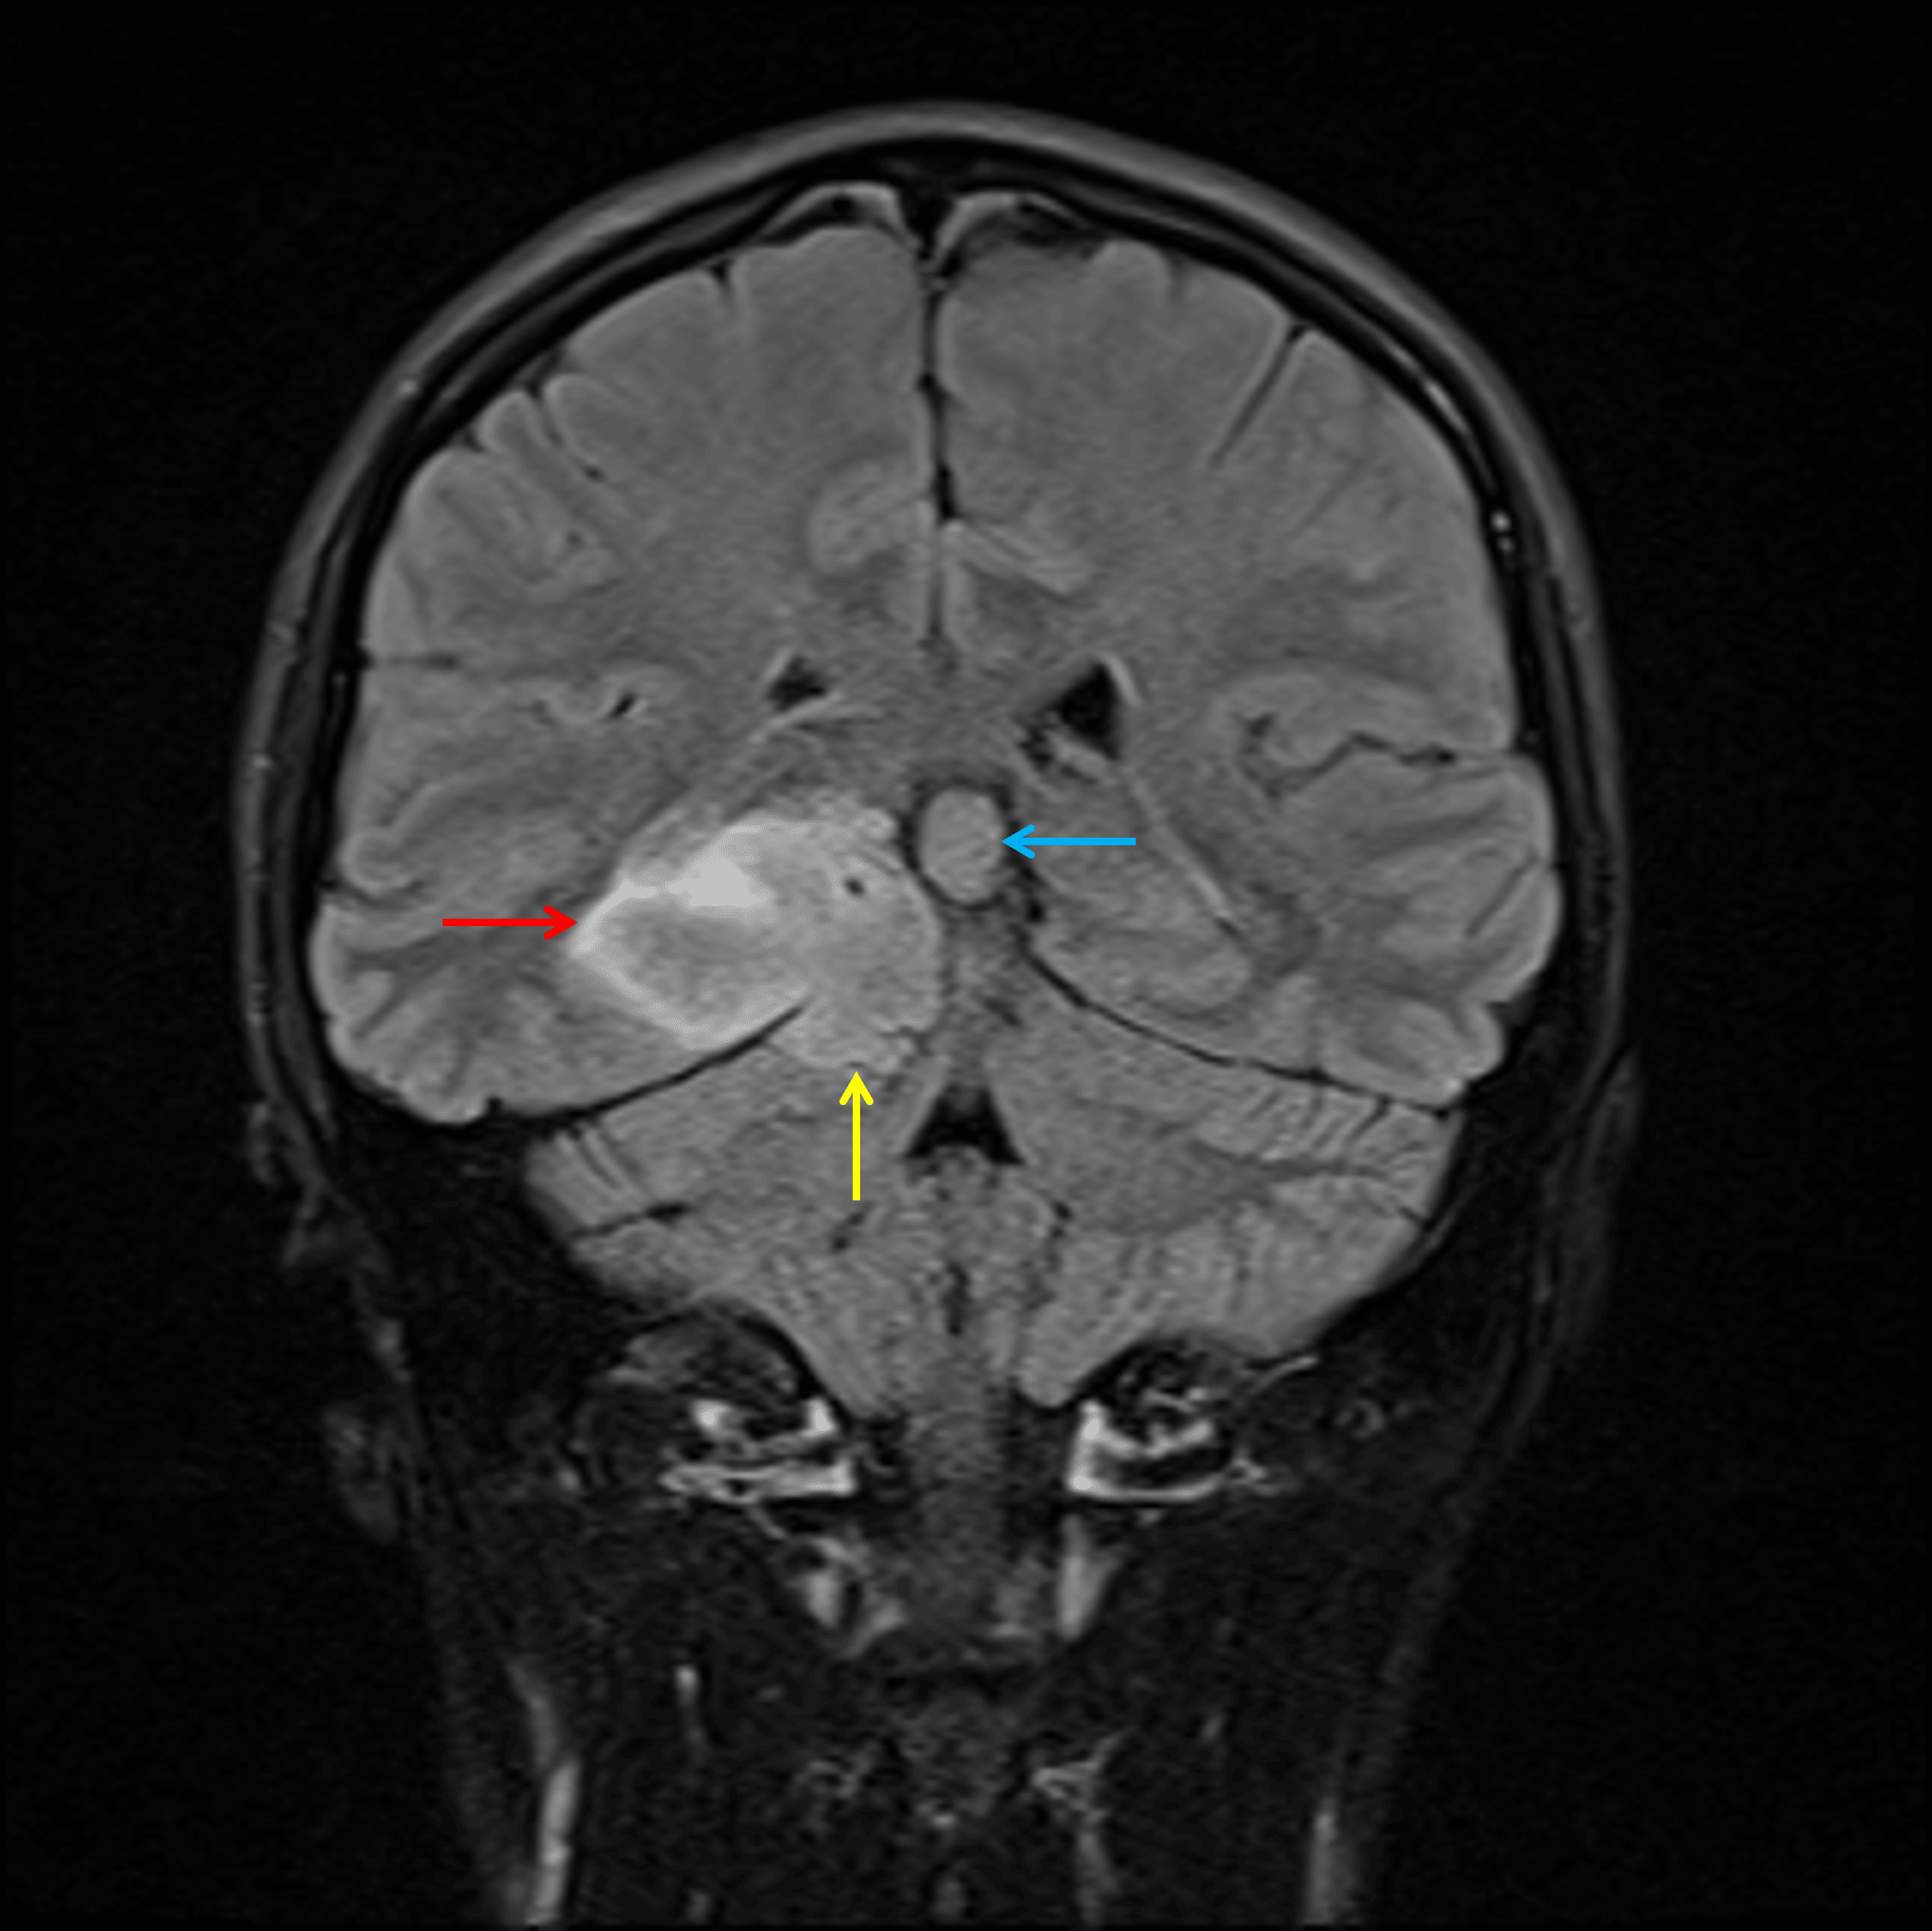

• Lobular T1 hypointense, T2 hyperintense mass centered in the medial right temporal lobe (with involvement of the hippocampus and parahippocampal gyrus) measuring 4.5 x 4.3 x 3 cm

• The mass bulges inferiorly through the tentorial notch and contacts the superior margin of the cerebellum

• Incomplete internal signal suppression on FLAIR

• No corresponding restricted diffusion or enhancement

• No surrounding parenchymal edema

• Associated local mass effect without evidence for hydrocephalus

• 1.4 cm pineal cyst

Solid mass in the medial right temporal lobe (red arrow), which bulges inferiorly through the tentorial notch (yellow arrow). Note that there is partial internal signal suppression on FLAIR compared to T2. Incidental pineal cyst (blue arrow).